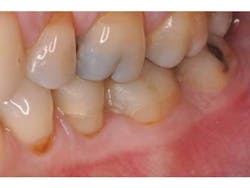

A patient presents with splinted provisional crowns on teeth Nos. 29 and 30 (Fig. 1). The provisionals were splinted to aid retention during the laboratory fabrication phase. The treatment plan called for all-ceramic restorations that could take advantage of resin cement bonding technology, thus the preparation margins were kept supragingival. Lithium disilicate restorations (e.max, Ivoclar) were created monolithically, meaning that no veneering feldspathic porcelain was required (Fig. 2).